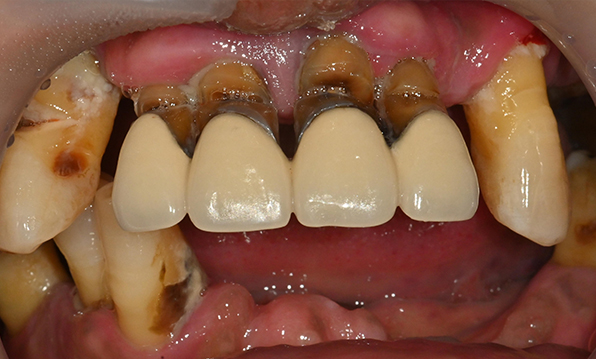

치아가 하나도 남아있지 않거나 전체적으로 상실된 경우 추천합니다.

전체 임플란트가 필요한 경우

치아가 얼마 남아있지 않은 경우

치주질환이 심해, 치아가 있더라도 제 기능을 하지 못하는 경우

틀니 사용이 불편한 경우

잇몸뼈가 얇은 상태

잇몸뼈 충분히 이식 후 임플란트 식립

성공을 위한 노하우, 잇몸뼈 재건 기술

전체 임플란트를 해야하는 환자들은

대부분 고령의 환자들로 오랜 틀니 사용

또는 노화로 인해 치조골이

거의 남아있지 않는 경우가 많습니다.

이 때, 치조골 이식을 병행하여 잇몸뼈 재건 후 안정적인 임플란트 식립을 하고 있습니다.

치료기간 : 2021.04.12~2021.09.15